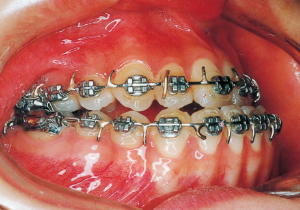

15 3-23-’91 Before surgery

16 5-9-’92 After Phase 2 Treatment

Pre-surgical orthodontic period: 9 months

Hospitalization period: 2 weeks

Intermaxillary fixation period: Approximately 1 month (orthodontic treatment was not possible during this period).

Post-surgical orthodontic period: 10 months